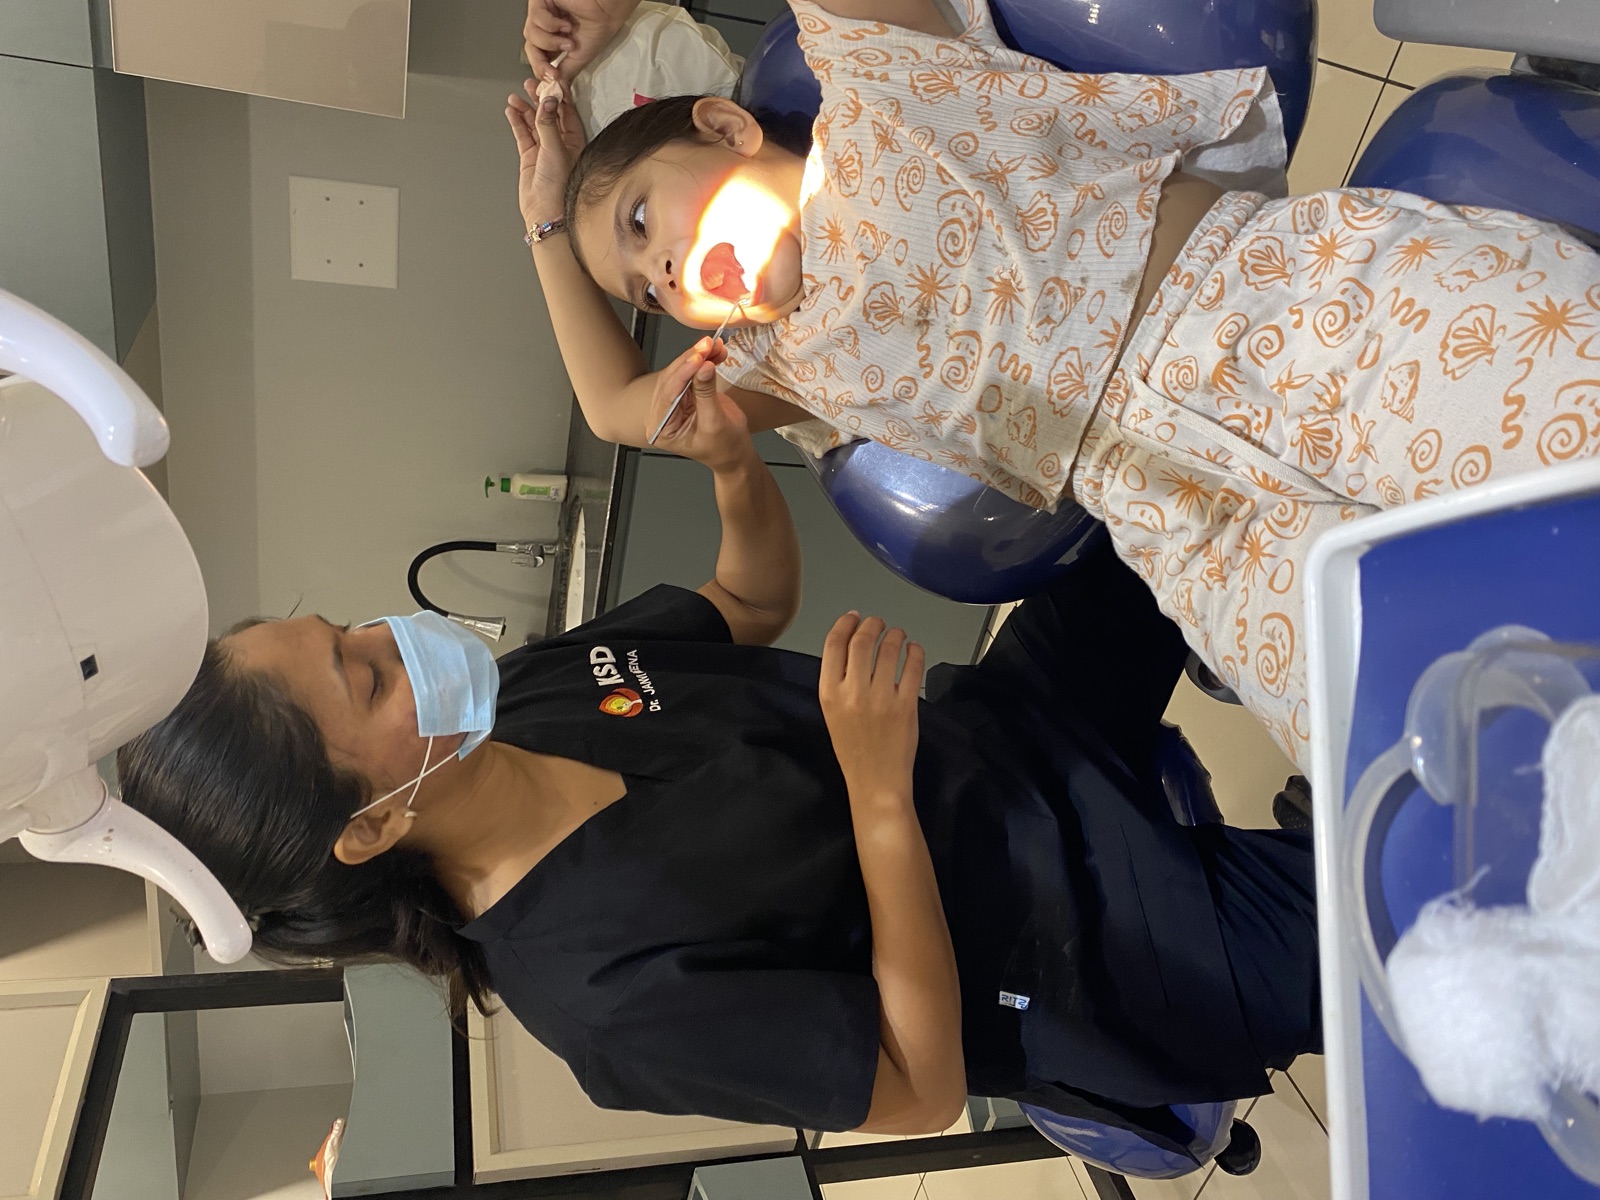

During. Mid-treatment: impression and bite registration for the lower complete denture, captured at the chair.